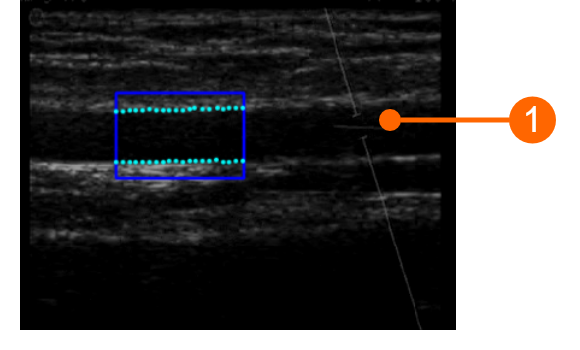

L'angolo compreso tra il fascio Doppler e l'orientamento del vaso dovrebbe essere ≤60 gradi. Il volume del campione dovrebbe essere il più ampio possibile ma senza includere le pareti del vaso e con un esiguo margine di errore in caso di movimento. Prestare attenzione che il cursore del volume del campione doppler (1) non sia nella ROI in cui viene calcolato il diametro. Si raccomanda che il volume del campione sia a 5 - 15 mm di distanza dalla ROI.

images/download/attachments/381258618/cvs_setupDuplex_bmode_gliffy-version-1-modificationdate-1759328517224-api-v2.png

ATTENZIONE: prestare attenzione che nella ROI vi sia solo l'immagine ecografica. Si prega di notare che l'elaborazione potrebbe essere influenzata da annotazioni o da qualsiasi altro oggetto grafico sovrapposto all'immagine. In particolare, prestare attenzione che il cursore del volume del campione doppler non sia nella ROI.